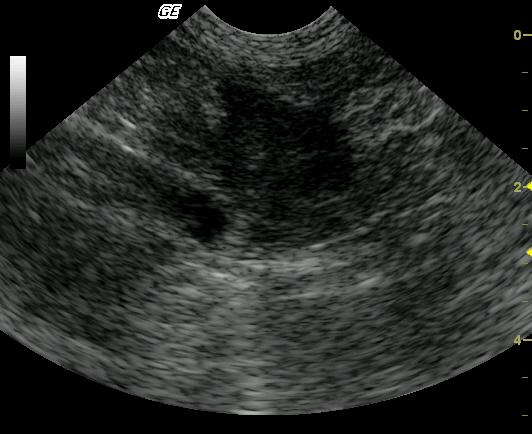

This 14-year-old FS DSH was presented for lethargy and vomiting. The physical exam revealed icterus, dehydration, and emaciation with thickened bowel loops and irregularly shaped kidneys on palpation. The CBC revealed only elevated absolute monocytosis while blood chemistry results revealed a markedly elevated ALT, markedly elevated lipase, and markedly elevated total bilirubin, with moderate azotemia, hyperglycemia and low T4. Urinalysis findings included 3+ bilirubinuria, spec gravity of 1.032, and cocci bacteria.